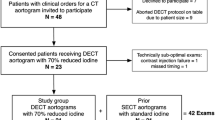

The mean aortic attenuations of FBP and AIDR images were not significantly different from each other. However, there was a 23 % reduction in image noise and a 28 % increase in CNR of the AIDR images compared with FBP images (Table 3). Figure 1 shows an example of image noise between FBP and AIDR images and the corresponding standard-tube-voltage image for comparison.

CT aortography of a 79-year-old male patient (weight 70 kg, BMI 27 kg/m2) after abdominal endovascular aortic repair. The first column shows axial images from the thorax, upper abdomen, and abdomen through an aortic stent at standard tube voltage (120 kVp, 100 ml contrast medium), the second column at low tube voltage using filtered-back projection (FBP) reconstruction (80 kVp, 40 ml contrast medium), and the third column at low tube voltage using adaptive iterative dose reduction (AIDR) reconstruction. The window level, 150, and window width, 800, were kept constant. The AIDR images showed less noise, fewer streak artefacts, and smoother texture compared with FBP images